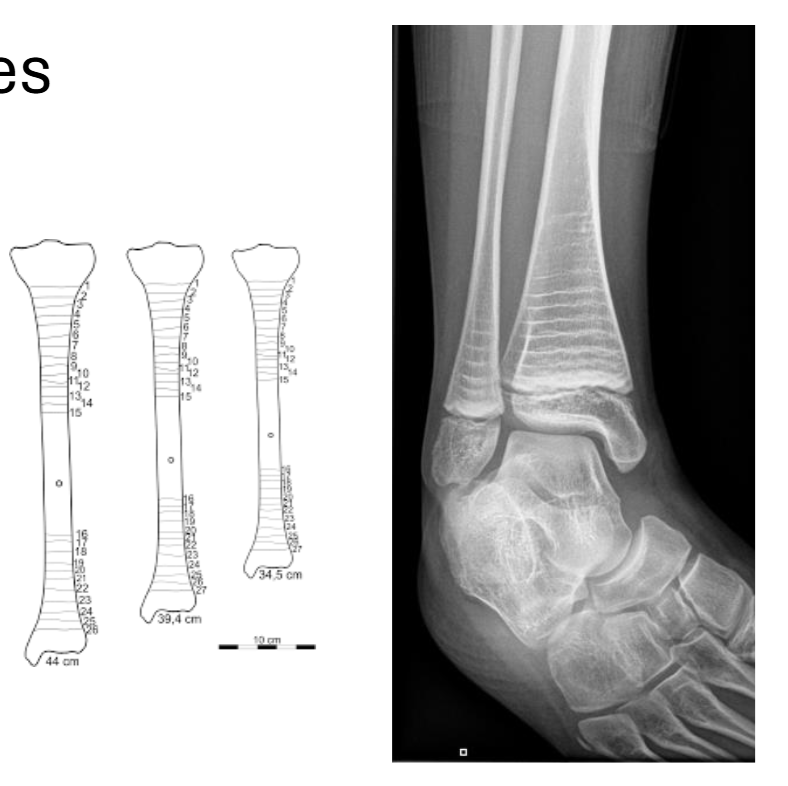

Force Fractures

Defines as the interruption of bone’s structure, as either a fissure or complete break.

Bones fracture in different ways because of difference in biomechanical force

Transverse Fracture

Fracture occurring from a force perpendicular to the bone’s main shaft (shear force)

Impacted Fracture

One end of the bone impacts the other end of the bone, and this force causes one end to jam toward the other (compression force)

Creates wedge-like fusion of bone

Compression force